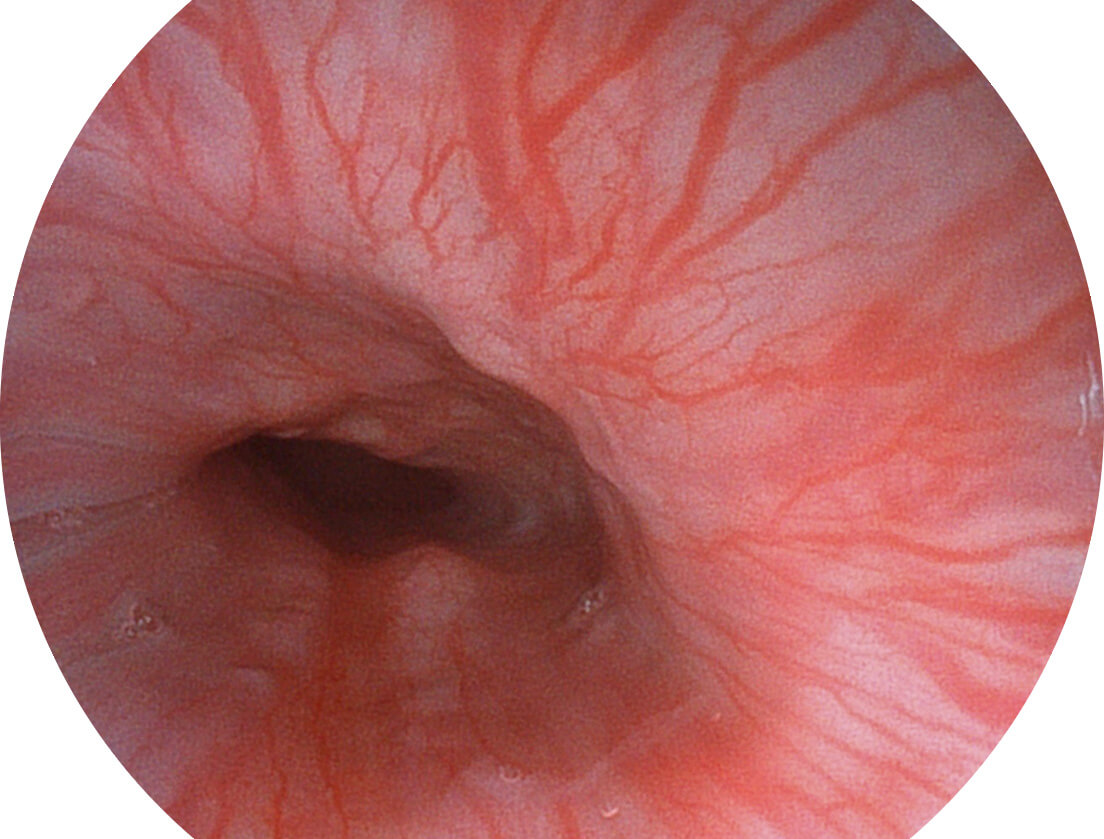

白光图像

VIST图像

Versatile Intelligent Staining Technology, VIST

强调浅层黏膜结构的同时,保证照明亮度和提升浅层微血管与中层血管颜色对比度,病变边界更清晰。